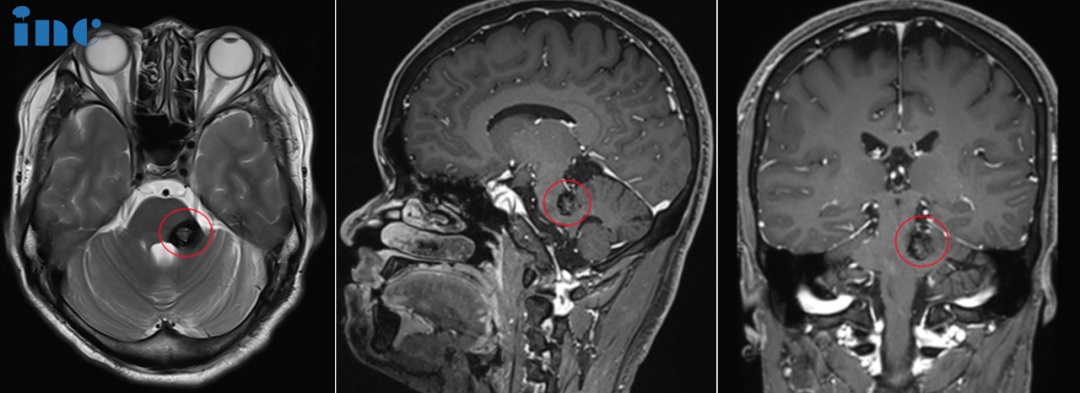

▼脑干海绵状血管瘤术前MRI